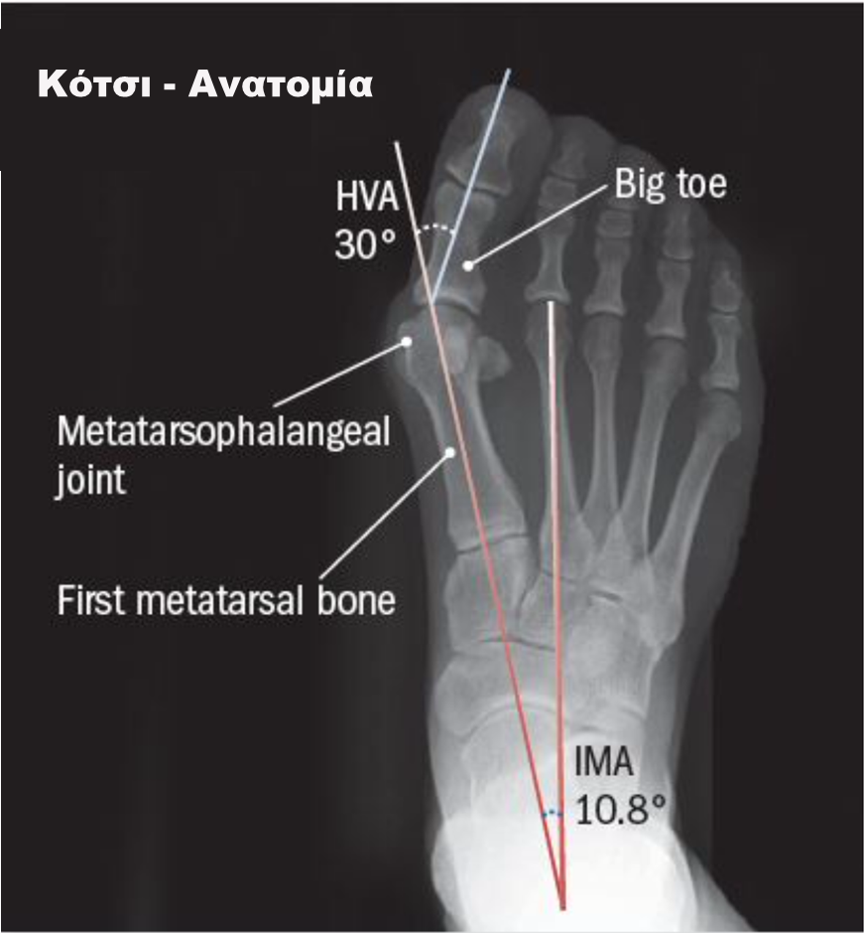

Το κότσι είναι μία παραμόρφωση στο μεγάλο δάκτυλο του ποδιού κατά την οποία το μεγάλo δάκτυλο κλίνει προς τα υπόλοιπα δάκτυλα, ενώ το πρώτο μετατάρσιο “στρέφεται” προς την αντίθετη κατεύθυνση.

Ο βλαισός μεγάλος δάκτυλος ή αλλιώς Κότσι είναι μια οστική παραμόρφωση στη βάση του μεγάλου δακτύλου στο έσω χείλος του ποδιού που συνήθως προκαλείται από απόκλιση του 1ου μεταταρσίου προς τα έσω και του μεγάλου δακτύλου προς τα έξω. Η περιγραφή της κατάστασης είναι απλή αλλά όχι τόσο απλή η θεραπεία της. Είναι συνήθης πάθηση αν σκεφτούμε ότι εμφανίζεται στο 40% περίπου του παγκόσμιου πληθυσμού.